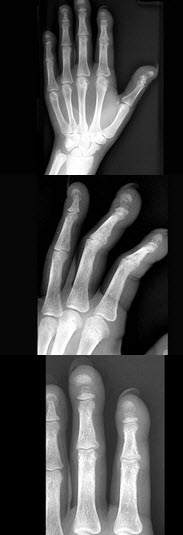

C.慢性胰腺炎

男,28岁,右上肢疼痛,夜间加重,服用止痛药可缓解,结合图像,最可能的诊断是()

A.骨瘤

B.骨软骨瘤

C.骨样骨瘤

D.骨囊肿

E.成骨细胞瘤